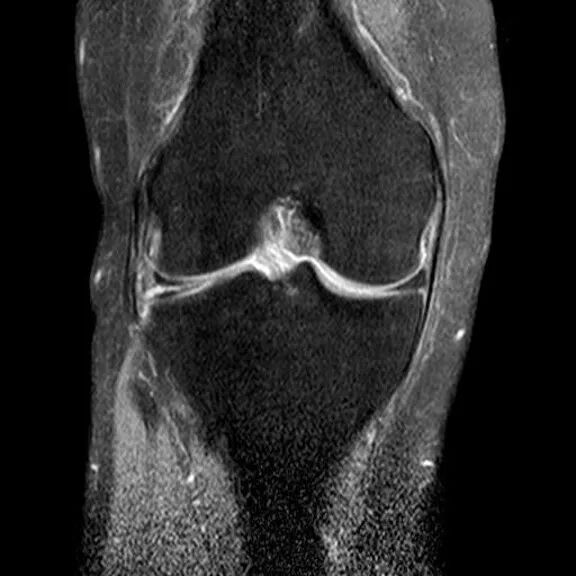

半月板桶柄状撕裂

1、多为纵形撕裂的特殊形式,有时来源于垂直(纵行)和水平撕裂2、多见于严重外伤的年轻患者3、内侧半月板发生率是外侧半月板的3倍

桶柄状撕裂MRI表现

1、宽度减小,在通过半月板体部的冠状面上蝶形消失,同时可见内移的半月板位于髁间窝、交叉韧带旁2、矢状面示残余的前角或后角变小或截断3、半月板前(后)角增宽或双半月板前(后)角征4、双前交叉韧带或双后交叉韧带征

桶柄状撕裂:宽度减小,在通过半月板体部的冠状面上蝶形消失,同时可见内移的半月板位于髁间窝、交叉韧带旁